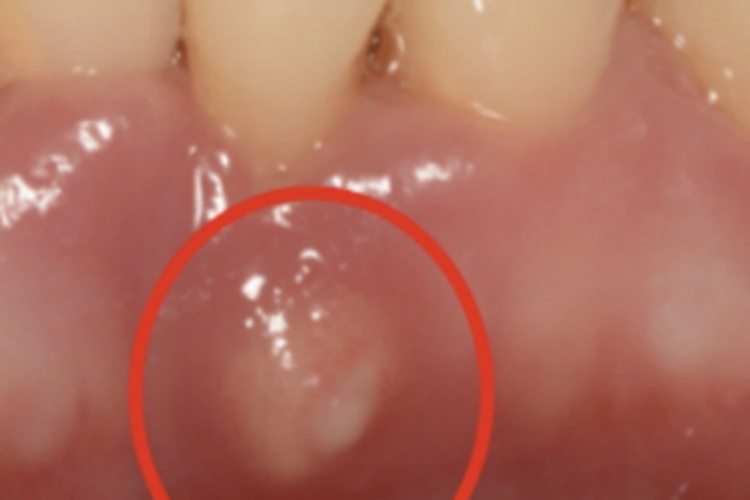

侵袭性牙周炎患者牙槽骨出现破坏,表现为局部牙槽骨突出,形成一个硬包。同时可出现牙列不齐的表现,活动期患者牙龈可呈鲜红色,进食硬物或刷牙可有出血症状。